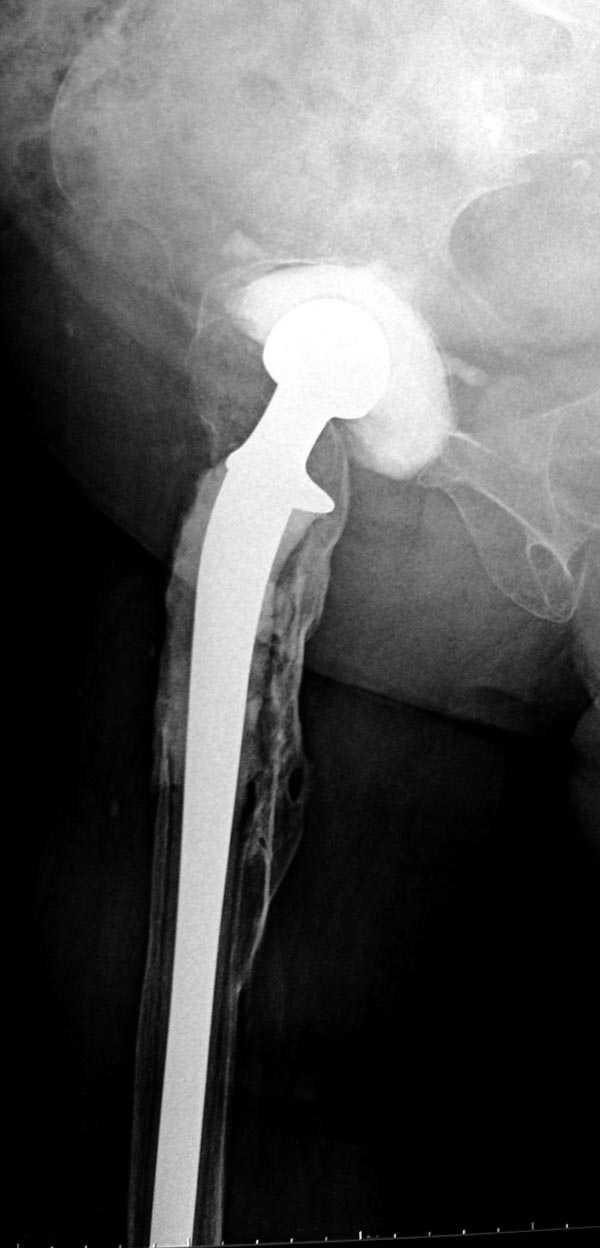

Как-то показывал случай после осложненного тотального эндопротеза, сперва из-за отсутствия экономических возможности, а затем привыкшая к своей участи вот уже более 8 лет ходит на временном "протезе-спейсере".

Полость вертлужной впадины и проксимальное бедро были заполнены custom made временным протезом из цемента.

Для бедренного компонента можно применить старую

длинную ножку протеза и желательно малого диаметра.